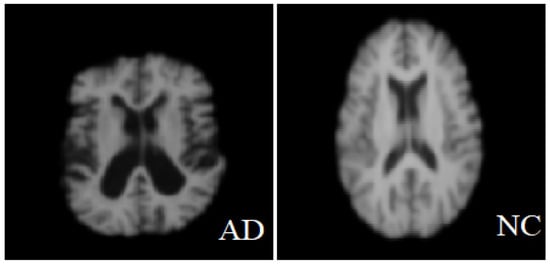

The MRI images used in this study were obtained from two publicly available datasets: the Alzheimer’s Disease Neuroimaging Initiative (ADNI) and minimal interval resonance imaging Alzheimer’s disease (MIRIAD). Official permission was secured for using the ADNI dataset, and no external image sources were used. The ADNI dataset is designed to monitor the early progression of Alzheimer’s disease and includes MRI scans with 128 sagittal slices, typically formatted as 256 × 256 matrices. It comprises data from 741 participants, including 314 AD patients and 427 normal controls subjects. The MIRIAD dataset includes MRI images of 46 AD patients and 23 normal controls, scanned at time points between 2 weeks and 2 years [,]. In this study, all image processing, model training, and evaluation were performed exclusively on sagittal slices due to their consistency and suitability for analysis. Axial slices were used solely for visualization purposes in Figure 2, given their higher display quality. The figure illustrates examples of benign and malignant images from both ADNI and MRTIAD datasets, helping to visually distinguish between the two diagnostic categories. Table 2 groups the samples by dataset and class (Alzheimer’s disease—AD and control—NC), showing the total number of samples for each category, and then shows their distribution into training (70%) and test (30%) sets.

Figure 2.

Two examples of malignant and benign Alzheimer’s images [].